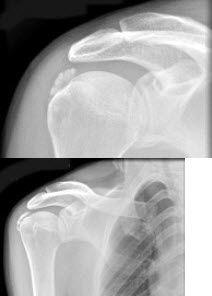

184、单项选择题

男,52岁,肩痛四月余,手臂旋转时疼痛加剧,结合影像,最可能的诊断是()

A.软骨瘤

B.骨结核

C.冈上肌腱钙化

D.骨囊肿

E.骨脓肿